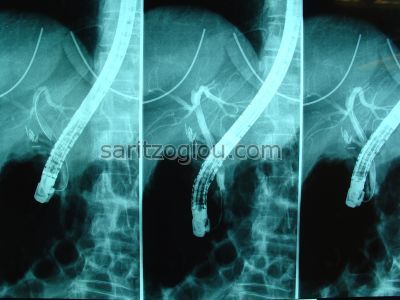

Μετά λαπαροσκοπική χολοκυστεκτομή διαπιστώθηκε λιθίαση χοληδόχου πόρου. Αφαίρεση του λίθου με καθετήρα μπαλόνι. Αναγνωρίζονται το λαπαροσκοπικά clips στον κυστικό πόρο και στην μεσαία εικόνα ο λίθος αμέσως κάτω από το ενδοσκόπιο.